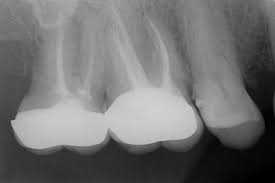

Periapical x-rays.

A periapical x-ray shows entire tooth starting from the crown to the root tip. It help your dentist to diagnose tooth decay, gum disease, bone loss or any other abnormalities in your tooth and surrounding Bone and tissues.